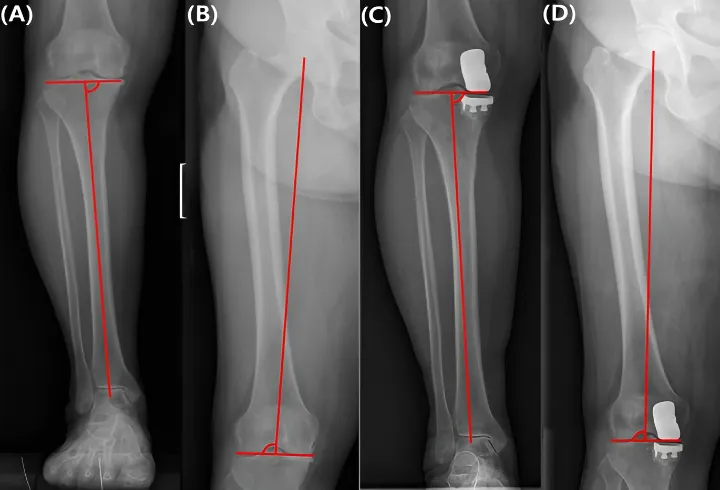

The Role of PACS in Knee

Modern knee diagnostics rely heavily on imaging — from X-rays to MRI — and this is where PACS (Picture Archiving and Communication System) plays a crucial role. PACS allows healthcare providers to store, access, and share medical images quickly and securely, ensuring faster diagnosis and smoother collaboration between specialists. Cloud-based PACS solutions, such as Studycast, make this process even more efficient by enabling clinicians to review images from any location without the limitations of traditional onsite systems.”